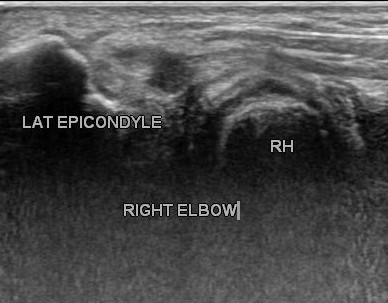

Steroid injections are locally effective anti-inflammatory medicines to relieve symptoms without harm. Corticosteroid injection helps when physical therapy is not effective. Locally acting steroids are not harmful as these are not water soluble, hence not absorbed in blood stream immediately. Ultrasound guidance is used for precision drug delivery to the center of inflammation or to the area of interstitial tear of tendon or partial traumatic tear as shown.